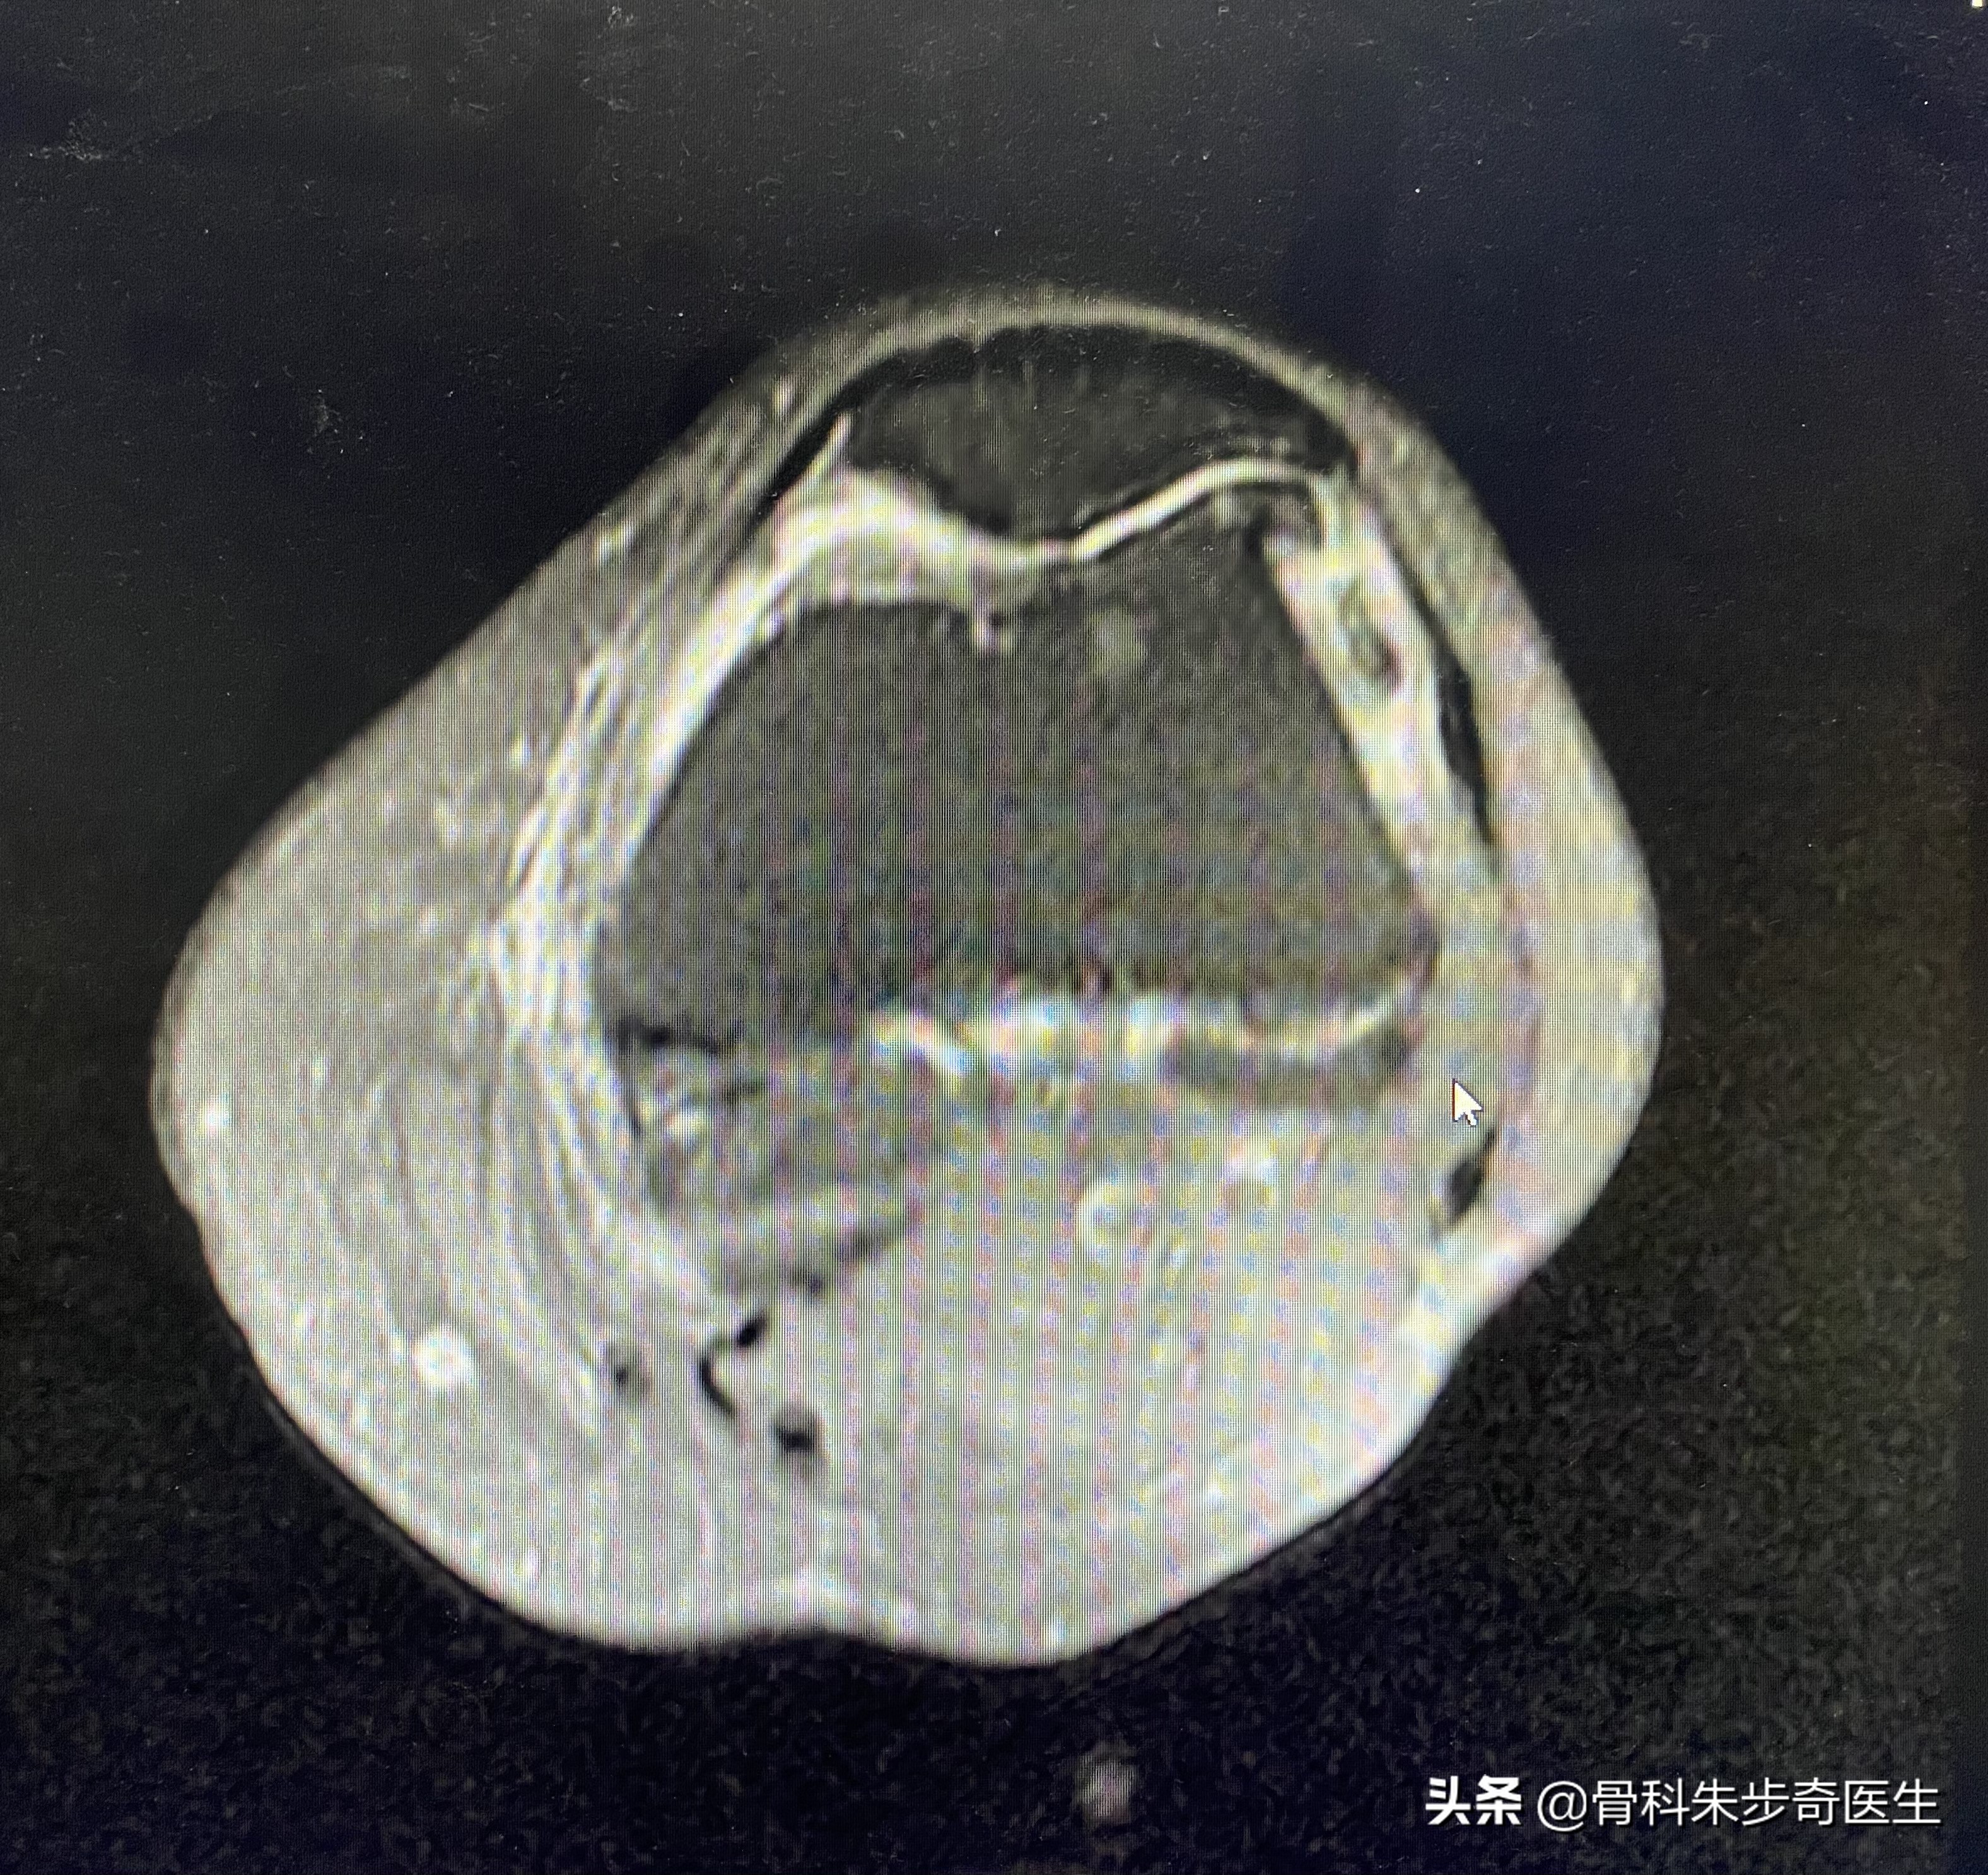

住院之后为了进一步搞清楚膝关节内部的问题,又做了一个核磁共振,结果如下:

看起来问题挺多,其实不管是软化,还是半月板撕裂,游离体,滑膜增厚,这些其实都是关节退变的表现。

根据这个情况,比较适合的是关节镜治疗,需要用关节镜把游离体取出来,同时观察膝关节内部的软骨,和滑膜情况,还可以清理一下内部的关节,所以建议她做膝关节的关节镜。

在镜下可以看到患者的软骨退变已经到达3期,存在软骨剥脱,将不稳定的软骨帮她去掉以防形成新的游离体,同时清理了滑膜,取出了现有的游离体,并冲洗了一下关节。